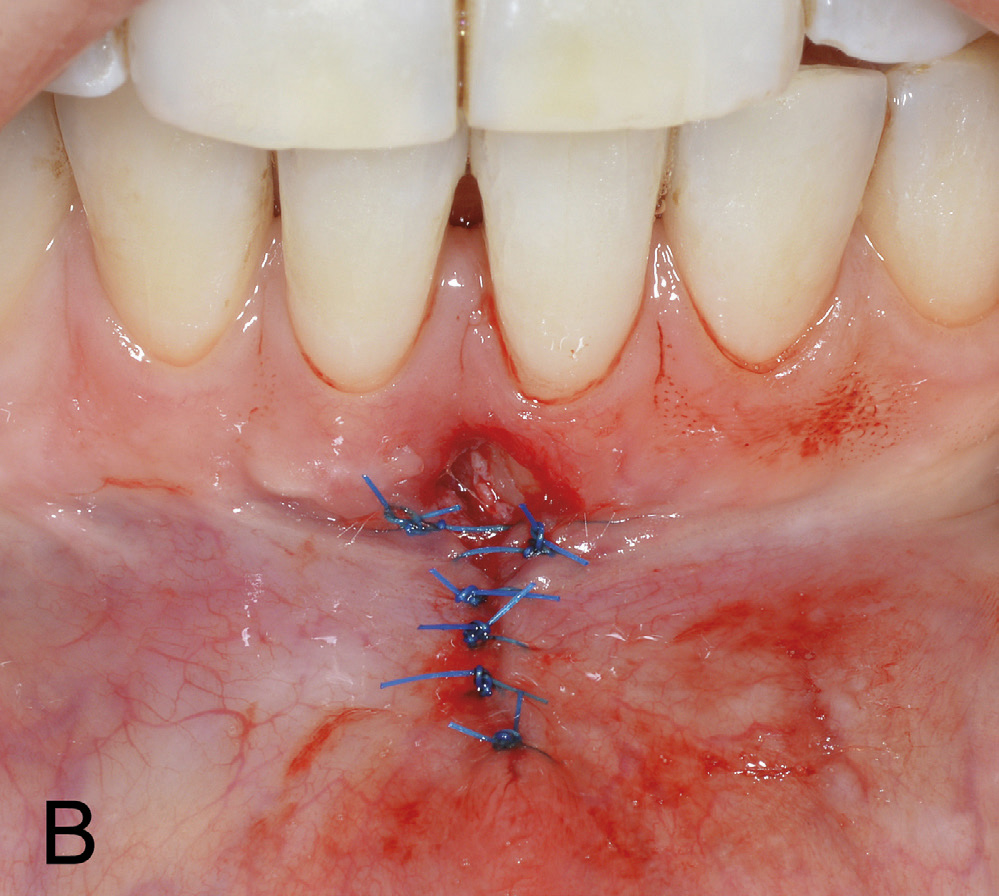

Basert på kliniske og røntgenologiske funn vart det i begge kjevar bestemt å instruera pasienten i atraumatisk børsteteknikk både lingvalt og labialt. På grunn av usikker prognose ved eit kirurgisk inngrep lingvalt vart det ikkje tilrådd å dekka retraksjonen 41 med eit ganetransplantat. For å redusera risikoen for utvikling av labiale retraksjonar, ville det ha ein førebyggjande effekt å fjerna drag frå frenulum (figur 1 B). Det vart difor bestemt å utføra ein frenektomi med eksisjon av marginale fiberdrag. Under inngrepet vart det diagnostisert ein dehisens labialt på 31 (figur 2 A). Etter eksisjon av periostfesta fiberdrag vart insisjonane freista lukka med seks enkle suturar (figur 2 B). På grunn av brei sårflate koronalt, vart det ikkje oppnådd fullgod sårlukking i festa gingiva. Dette resulterte i ei utilsikta eksponering av beindehisensen 31. Ved første kontroll, 7 dagar postoperativt, var det udekka området delvis lukka med sekundær tilheling. Ved suturfjerning 14 dagar postoperativt var dehisensen på 31 framleis eksponert (figur 3 A). Manglande sårdekning vart freista lukka med to nye suturar. Men ny kontroll etter 1 månad viste auka roteksponering 31 (figur 3 B). Ved postoperativ kontroll etter 1 1/2 månad hadde det marginale blautvevsbandet gått tapt og blautvevsdefekten utvikla seg til ein gingival retraksjon på 4 mm i horisontal og 3 mm i vertikal retning (figur 4).

Figur 2 A. Frenektomi underkjevefront med eksponering av rotdehisens 31.

Figur 2 B. Lukking av mukosadelen av insisjonen, men utan fullgod lukking av insisjonen i festa gingiva.